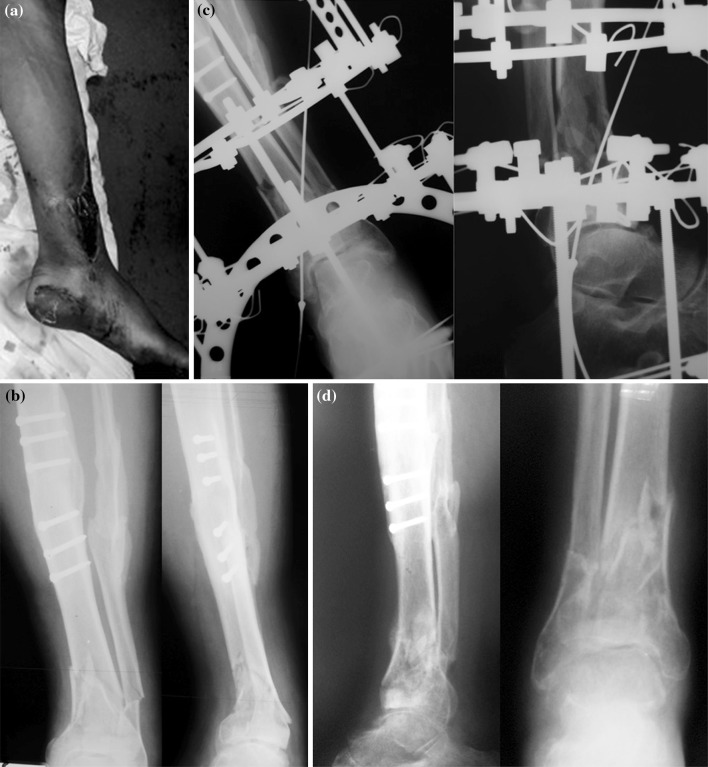

Fig. 2.

An example of a 56-year-old male with a 3B open Pilon type III fracture- treated with Ilizarov fixator. a Clinical picture, b preoperative X-rays, c X-rays 6 weeks post-operatively, d nine months post-operatively the fracture healed, and the frame was removed

The use of Ilizarov fixator is well established for limb salvage and complex fractures with severe soft tissue injuries [7, 11–14]. These principles were used for a mass casualty setting in a disaster zone (Fig. 2). These included adequate wound debridement, stabilization with plastic surgical coverage and early mobilisation. Despite difficulties that exist in such circumstances, this experience suggests that the application of basic Ilizarov principles in a disaster zone can be as effective as in established limb reconstruction and trauma units.